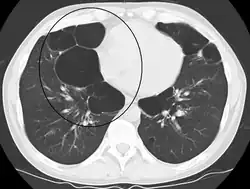

A CT scan is not routinely used except for the exclusion of bronchiectasis.[5] Pulse oximetry measurement of peripheral oxygen saturation is recommended in people with clinical signs of respiratory failure or right heart failure.[5] An analysis of arterial blood is recommended in those with a peripheral oxygen saturation of 92% or less to determine actual blood oxygen level and assess for high levels of carbon dioxide in the blood, which may have therapeutic implications such as need for non-invasive ventilation or oxygen supplementation.[10] WHO recommends that all those diagnosed with COPD be screened for alpha-1 antitrypsin deficiency.[40]

Axial CT image of the lung of a person with end-stage bullous emphysema -